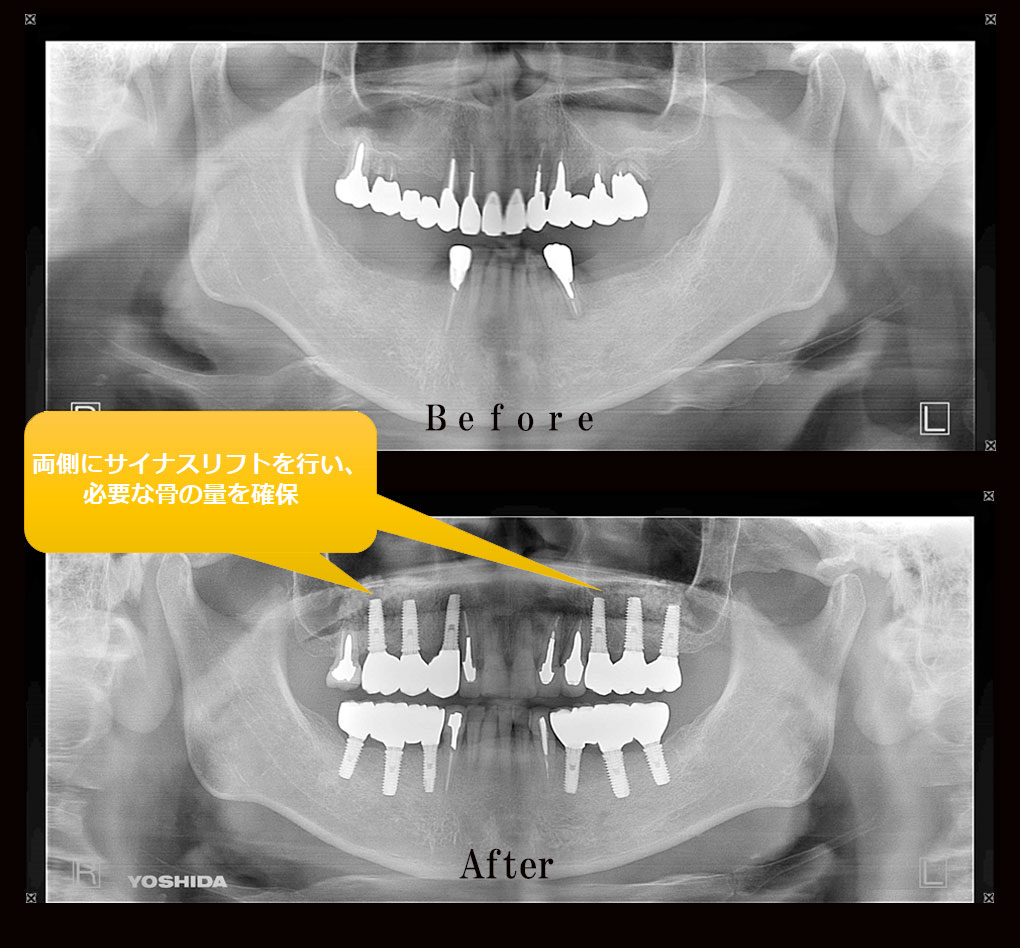

多数歯欠損ケース治療実績|実績・症例|朝霧 インプラント, 下顎多数歯欠損インプラント症例|症例解説|東京銀座シンタニ,

多数歯先欠・6歯以上の先天性部分無歯症の矯正治療, 多数歯欠損ケース治療実績|実績・症例|朝霧 インプラント【書籍概要】本書は、インプラント治療に関する専門的な知識を提供することを目的とした書籍です。特に多数歯欠損や無歯顎症例に焦点を当て、実践的な治療法や症例を詳述しています。【著者情報】著者は、インプラント治療の分野で豊富な経験を持つ専門家たちで構成されています。彼らの知識と技術が詰まった一冊です。【対象読者】この書籍は、歯科医師や医療従事者、インプラント治療に関心のある方々に最適です。専門的な内容が多く含まれているため、実務に役立つ情報が得られます。- タイトル: MAXILLA-ORIENTED IMPLANTOLOGY- 著者: 林 裕幸, 武田 幸之, 桜井 幸弥, 森田 謙治- 出版社: ゼニス出版- 言語: 日本語- テーマ: 多数歯欠損・無歯顎症例のインプラント治療ご覧いただきありがとうございます。

多数歯欠損ケース治療実績|実績・症例|朝霧 インプラント【書籍概要】本書は、インプラント治療に関する専門的な知識を提供することを目的とした書籍です。特に多数歯欠損や無歯顎症例に焦点を当て、実践的な治療法や症例を詳述しています。【著者情報】著者は、インプラント治療の分野で豊富な経験を持つ専門家たちで構成されています。彼らの知識と技術が詰まった一冊です。【対象読者】この書籍は、歯科医師や医療従事者、インプラント治療に関心のある方々に最適です。専門的な内容が多く含まれているため、実務に役立つ情報が得られます。- タイトル: MAXILLA-ORIENTED IMPLANTOLOGY- 著者: 林 裕幸, 武田 幸之, 桜井 幸弥, 森田 謙治- 出版社: ゼニス出版- 言語: 日本語- テーマ: 多数歯欠損・無歯顎症例のインプラント治療ご覧いただきありがとうございます。